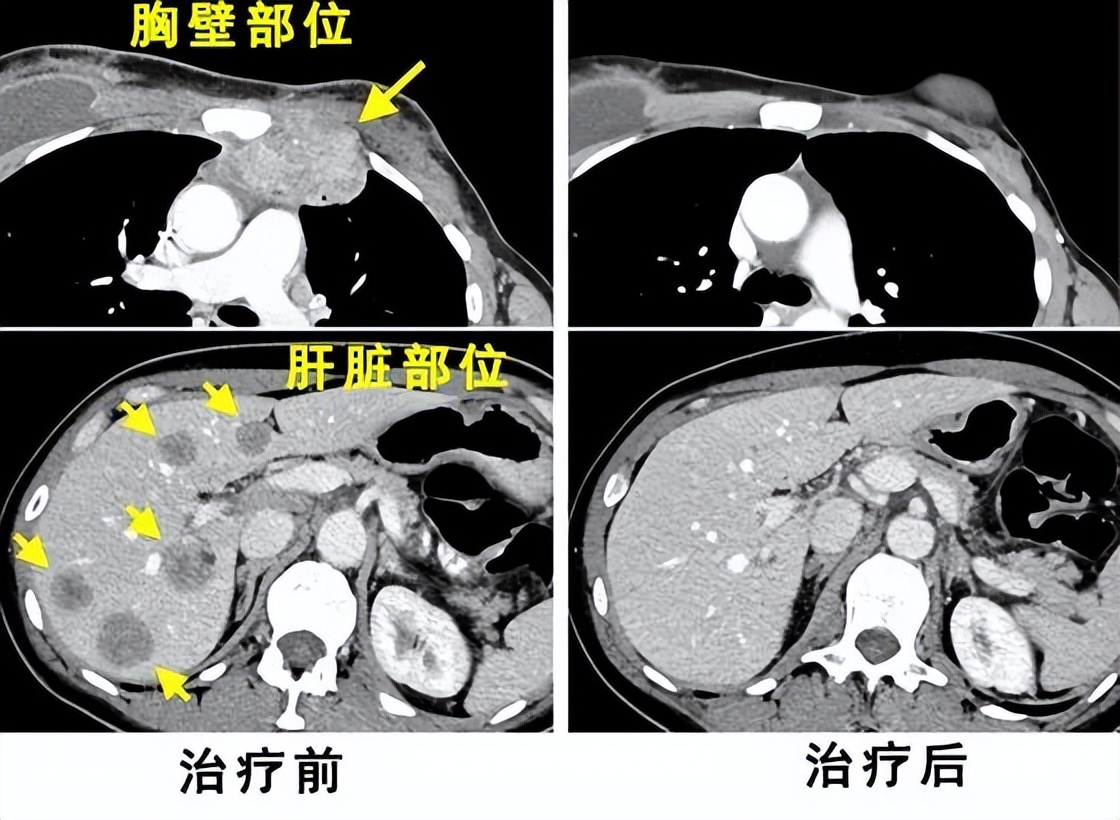

2015 年 8 月,她参与了TIL疗法临床试验当时科学家们采集了她体内抗肿瘤的免疫细胞。然后再将它们在实验室中进行繁殖,并在12月向她的体内注射800亿个免疫细胞。治疗几天后,珀金斯的肿瘤已经缩小到足以让她停止服用止痛药的程度。 到 2016 年 5 月,也就是她接受治疗五个月后,扫描结果显示她没有癌症。如今,朱迪·珀金斯已成功存活7年,免疫细胞让珀金斯实现了医学的奇迹。